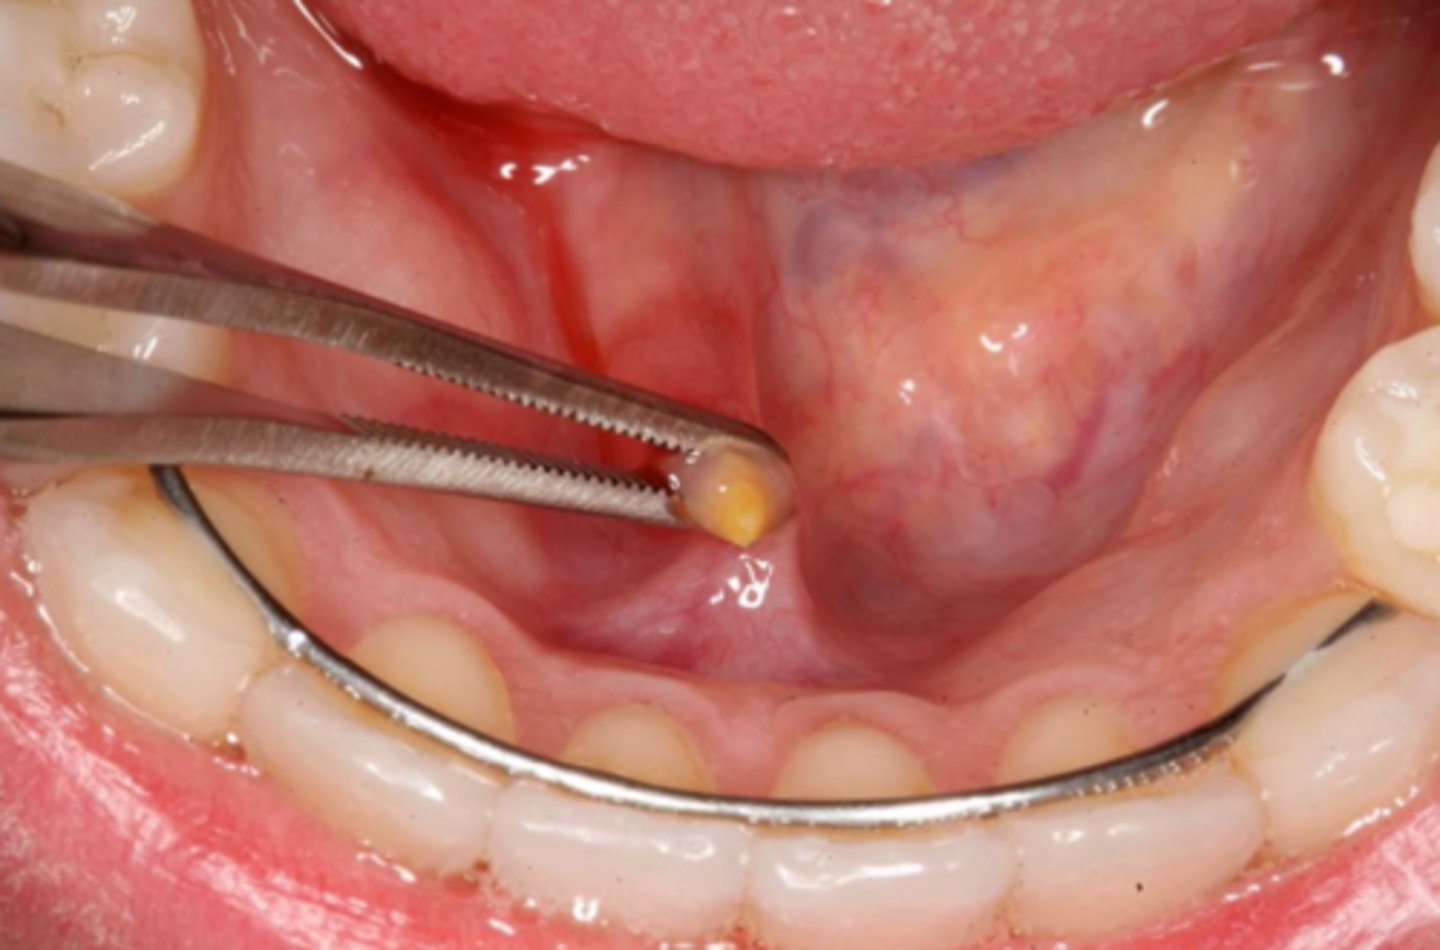

what is the calcified, round, yellow, hard mass structure within the salivary ductal system caused by the deposition of calcium salts around a nidus of debri within the lumen?

sialolith

what reactive salivary gland lesion most commonly occurs in the submandibular gland/duct due to the tortuous path of Wharton's duct and may be firm/hard?

sialolithiasis

how are small sialoliths treated? how are large sialoliths treated?

milking the stone out; need surgical removal (entire gland may need to be removed)

what reactive salivary gland lesion is treated with sialagogues, moist heat, and fluid intake to promote passage?